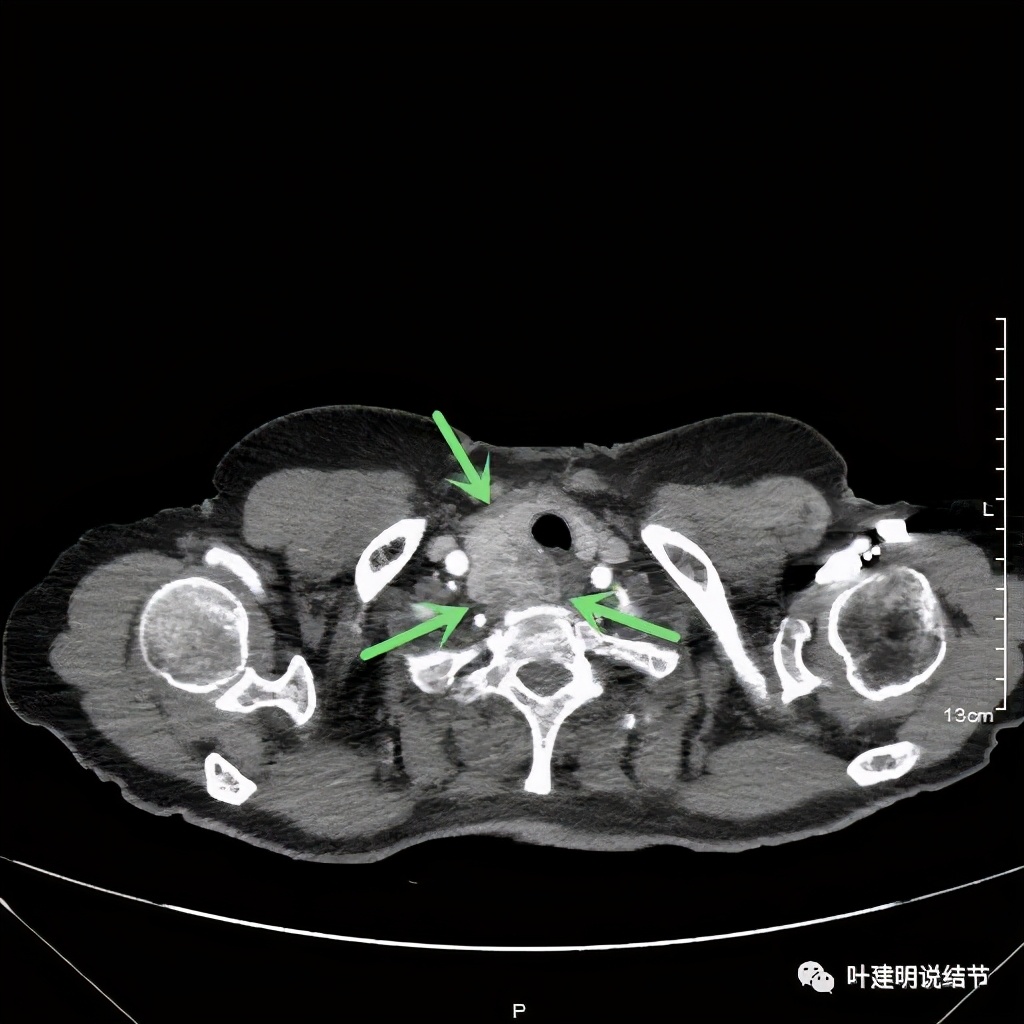

上图红色示肿瘤,黄色示气管,粉色示肿瘤与气管关系密切,桔色示左无名静脉,肿瘤密度不均

上图红色示肿瘤,黄色示气管,蓝色示上腔静脉

上图红色示肿瘤,黄色示气管,蓝色示上腔静脉,肿瘤已经快要消失了的层面,它距离隆突只有2点几厘米了,位置很低